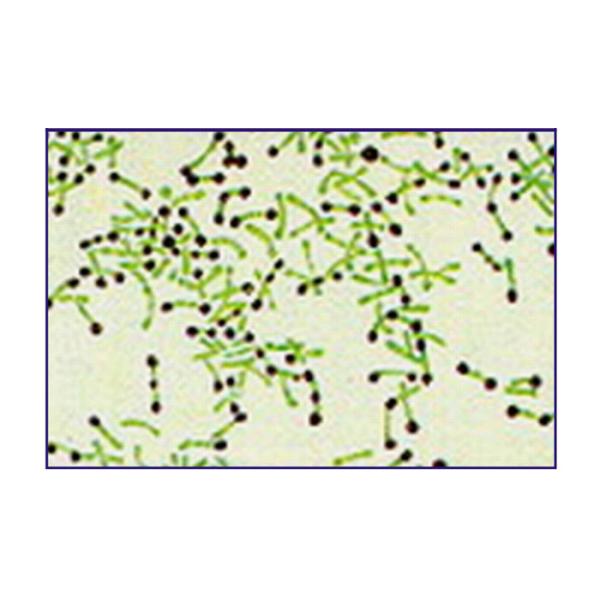

The size of Corynebacterium diphtheriae is very variable, essentially rod-shaped but often showing irregular expansion at one end. Cells frequently lie in small clusters at acute angles to each other in V, L or Y shapes. Gram positive but readily decolorized, non-motile, non-capsulate, non-sporing.

Strains are distributed as beans and stained unevenly. With Metachromatic Granules Stain, deeply stained granules known as metachromatic granules, are found on one side or both sides of diphtheriae.